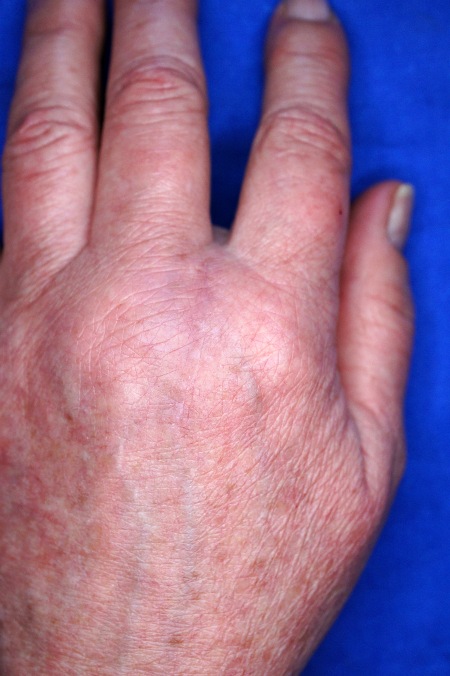

Fortgeschrittenes Karpaltunnelsyndrom mit trockener, rissiger Haut der ersten 3 Finger. Hautcreme befand sich immer in der Handtasche der Patientin

Fortgeschrittenes Karpaltunnelsyndrom mit trockener, rissiger Haut der ersten 3 Finger. Hautcreme befand sich immer in der Handtasche der Patientin